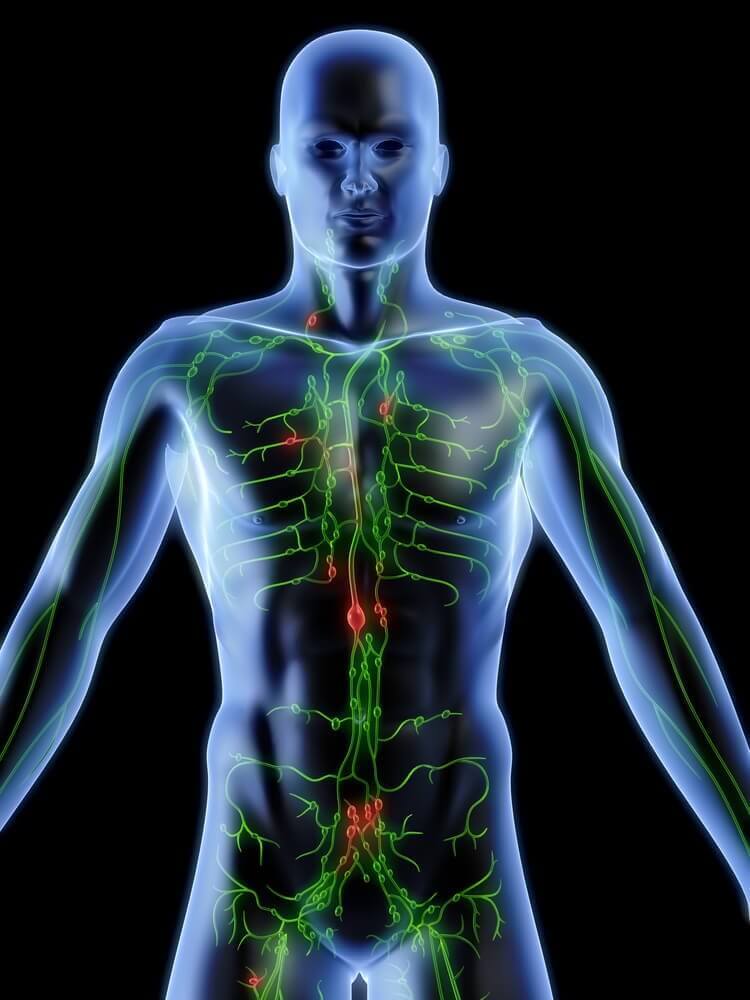

림프계는 순환계와 비슷하지만, 이와 다르게 한쪽으로만 흐른다. 몸의 세포 조직에서 시작해서 림프관을 따라 혈액에서 끝난다. 그렇기 때문에 림프계를 정화하는 일은 중요하다. 림프계는 자체적으로 독소를 제거하지만 정기적으로 정화 과정을 거치는 것이 좋다. 이 글에서는 림프계를 정화하는 5가지 식물성 솔루션을 소개한다.

림프계는 신체의 필수적인 부분으로서 몸 전체로 확대되는 가는 혈관인 림프관으로 이루어져있다. 이 관들은 백혈구와 림프구를 포함하는 림프라는 투명한 액체를 분비한다.

림프계는 아래의 역할을 한다.